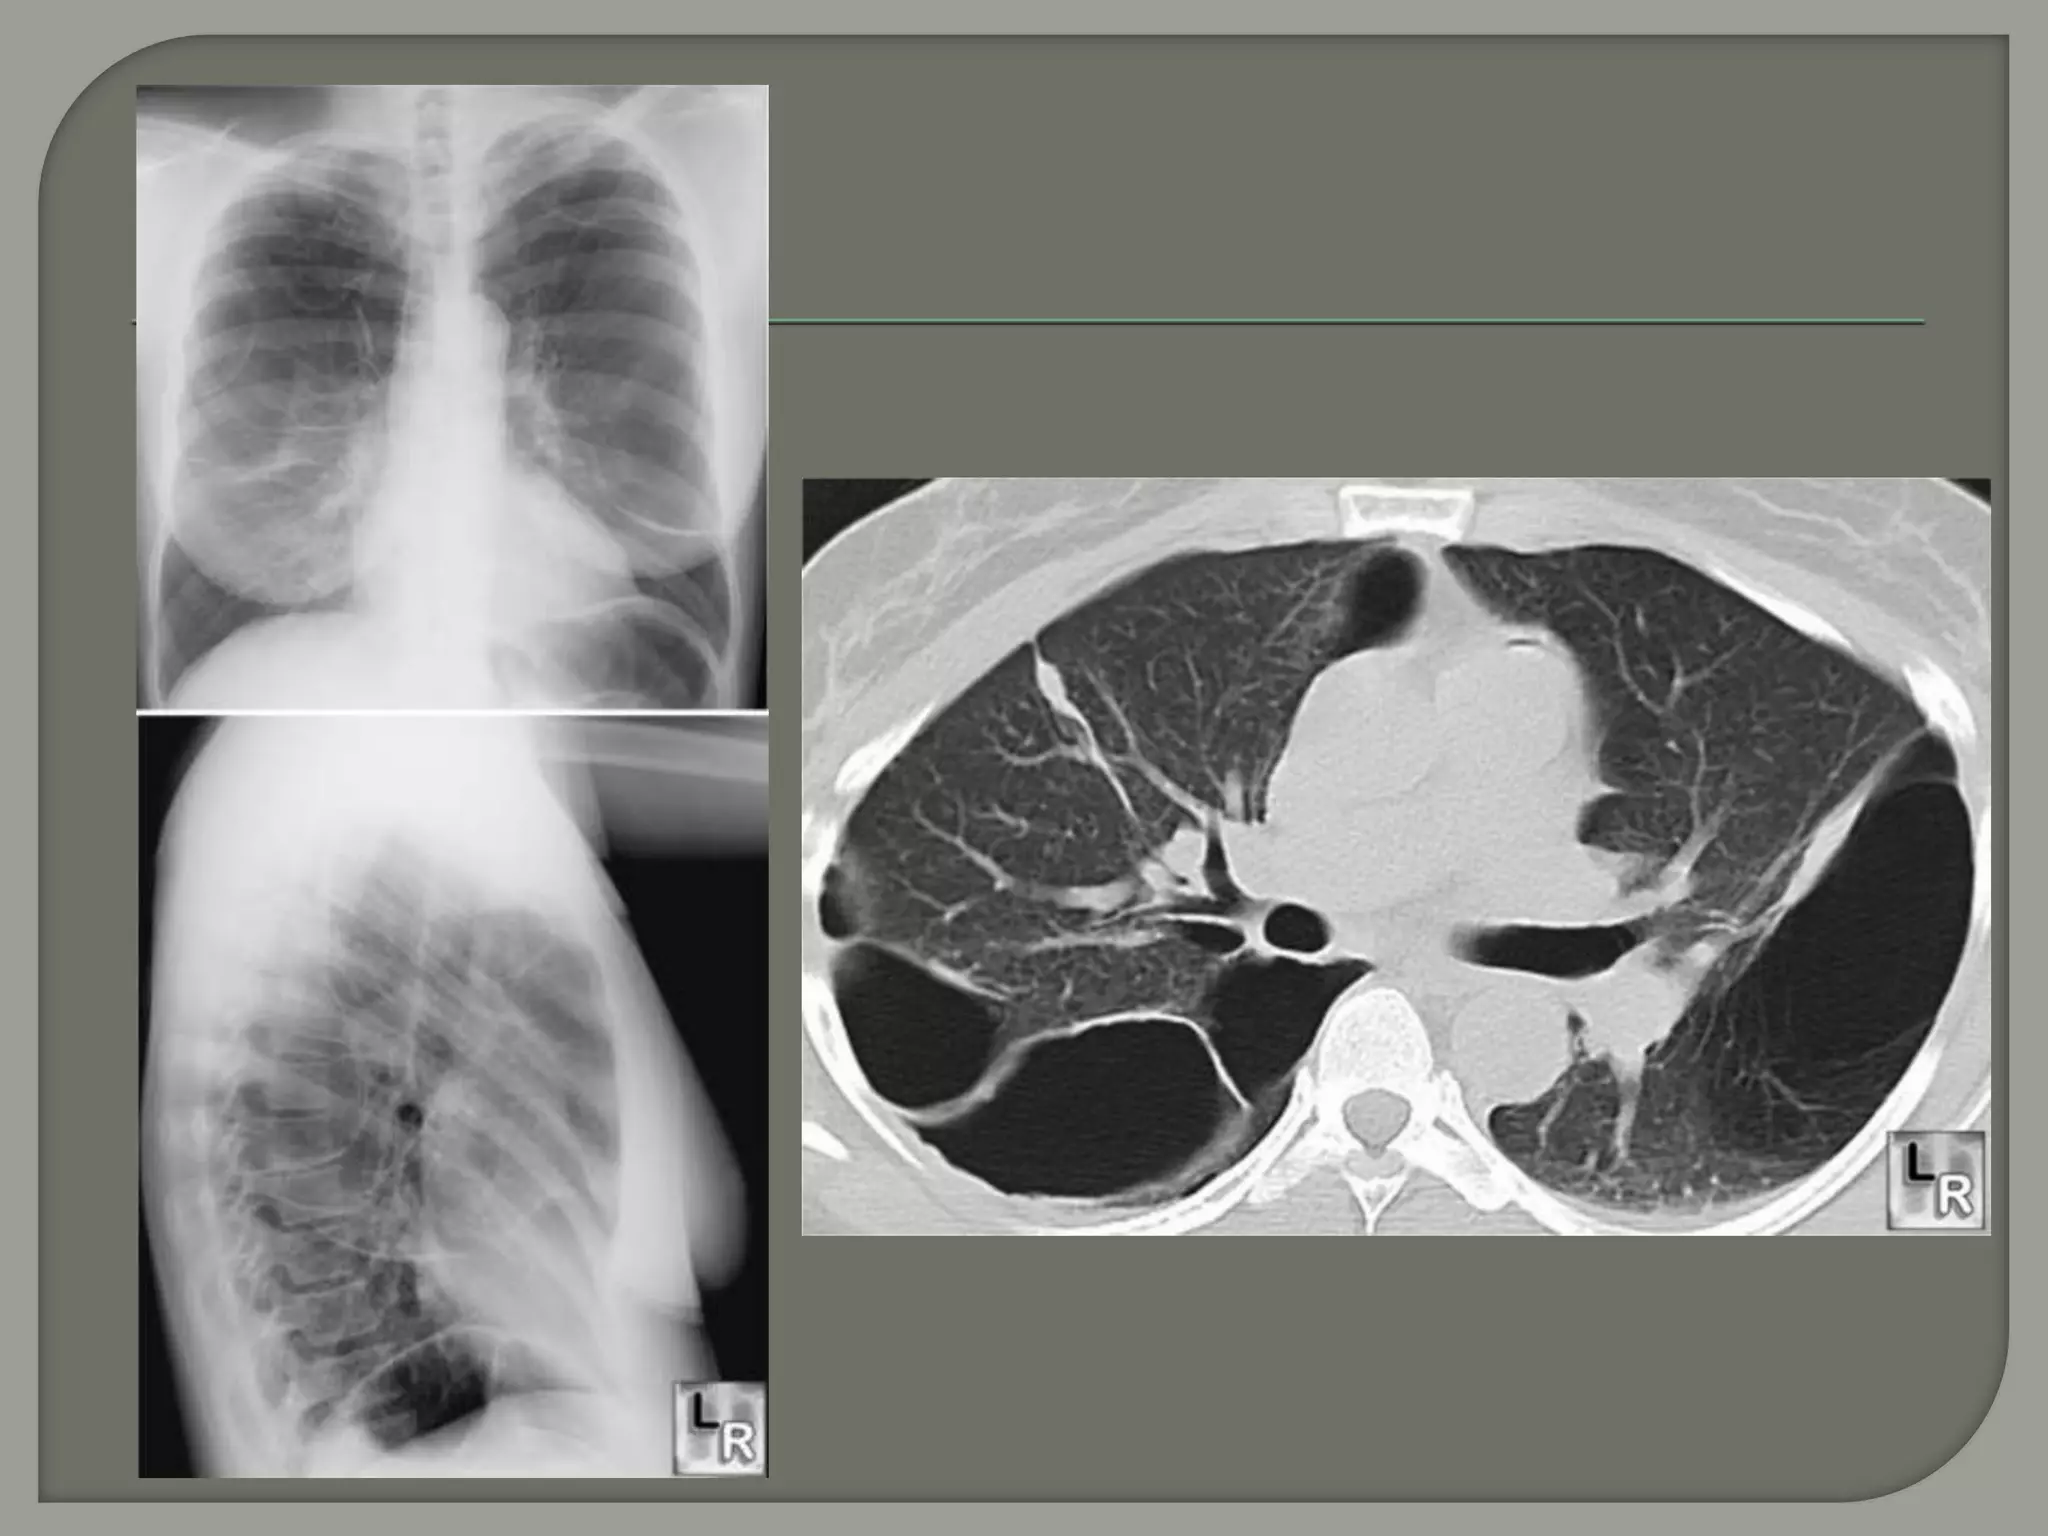

CT image of

the lungs

demonstrating

the right lower

lobe bulla with

compressed

lung

Giant bullae are predominantly located in the

upper lobes and generally subpleural.

However, in patients with

α1-antitrypsin deficiency, bullae are most

commonly located at the lung bases.